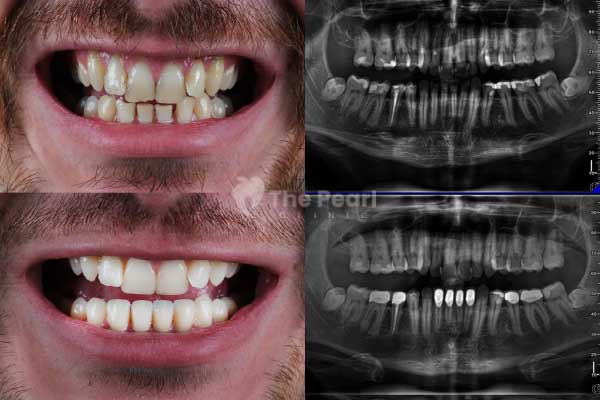

A filling, also known as a dental filling, is the most commonly used treatment method in the early stages of cavity treatment. It involves removing the affected tissue and leaving a space to be filled with a biocompatible material later. This process rehabilitates the damaged part of the tooth, restoring its functionality and original appearance.

What Material Is Used for Fillings and How Long Do They Last?

There was a time when smiles were filled with silver and even gold decorations. In the past, highly durable silver amalgam materials were used. However, their negative aesthetic effects have led to the adoption of newer materials. Primarily, we refer to composites. These are a type of resin that matches the color of the bone like the tooth. As mentioned earlier, composites fill the void, and since they harden with light, they are cured with a special light.

The downside is that composites are less durable than metal fillings. However, this does not mean you have to change your fillings every week. During periodic check-ups, the dentist will tell the patient when the old filling needs to be replaced. Depending on the patient's care, bite, and other personal conditions, a composite filling can last for many years.